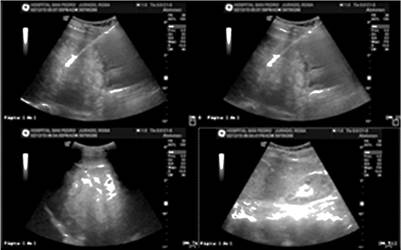

Se le realizan paraclínicos, con cuadro hemático dentro de parámetros normales, PCR elevada: 15 mg/dL, electrólitos, función renal, glucemia y tiempos de coagulación dentro de los valores normales. Ecografía de hígado y vías biliares que reportó múltiples lesiones focales de posible origen metastásico (Figura 1).

Figura 1 Ecografía de hígado y vías biliares. Múltiples lesiones focales de posible origen metastásico.

Cuando se sospecha metástasis de melanoma en el tracto digestivo se debe llevar a cabo el diagnóstico por imágenes apropiadas. La primera etapa básica de diagnóstico es la ecografía abdominal, este es un examen no invasivo y de bajo costo. Otro examen es la tomografía computarizada, cuya sensibilidad de identificación de metástasis de melanoma en el tracto digestivo es solo de 60%-70%. En cada caso, cuando las metástasis en el tracto digestivo se sospechan clínicamente, es necesario llevar a cabo otros exámenes a pesar de TAC negativo. El examen PET/TC garantiza mayor sensibilidad que la TAC en la identificación de metástasis de melanoma y debe llevarse a cabo si está disponible 4. En el reporte de caso, la ecografía y la TAC revelaron metástasis en el tracto digestivo (Figura 1 y 2).